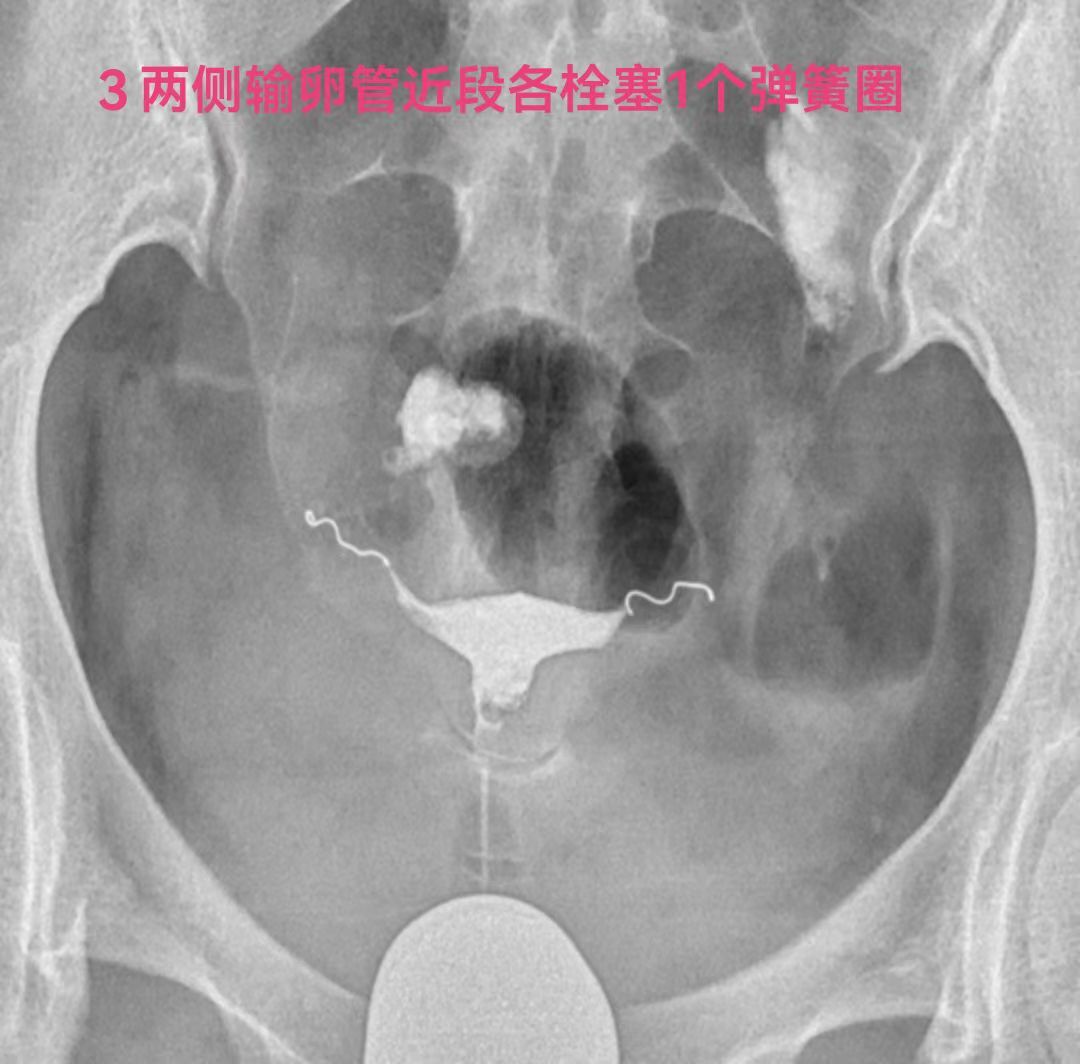

因此致密栓塞不仅是多花钱多受罪,而且还没有栓塞一个合适的弹簧圈栓塞的严实。请看下图双侧输卵管积水两侧输卵管各栓塞一个弹簧圈的术前术后标识。

下面是一例双侧输卵管积水做试管婴儿,2017年在胚胎移植前我给她两侧输卵管各栓塞一个弹簧圈,后来移植后还是双胎。